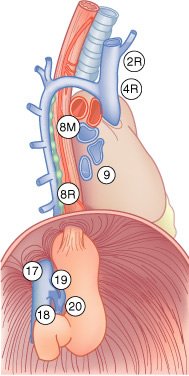

Mapa de linfonodos para câncer esofágico. A, Visão anterior. B, Visão lateral esquerda. C, Visão lateral direita. Estações ganglionares: l, supraclavicular; 2R, paratraqueal direito; 2L, paratraqueal esquerdo; 3P, mediastinal posterior; 4R, ângulo traqueobrônquico direito; 4L, traqueobrônquico esquerdo; 5, aortopulmonar; 6, mediastinal anterior; 7, subcarinal; 8M, paraesofagiano médio; 8L, paraesofagiano inferior; 9, ligamento pulmonar inferior; 10, hilar; 15, diafragmático; 16, paracardial; 17, gástrico esquerdo; 18, hepático comum; 19, esplénico; 20, celíaco A falta de serosa do esôfago tende a favorecer a extensão local do tumor.

A extensa drenagem linfática mediastinal, que se comunica com os vasos colaterais cervicais e abdominais, é responsável pelo achado de metástases ganglionar, mediastinal, supraclavicular ou do tronco celíaco em, pelo menos, 75% dos pacientes com carcinoma esofágico. Cânceres do esôfago cervical drenam para os linfonodos cervicais profundos, paraesofágicos, mediastinais posteriores e traqueobrônquicos. Os tumores do terço inferior disseminam para os linfonodos paraesofagianos, celíacos e do hilo esplénico. A disseminação a distância para fígado e pulmões é comum.